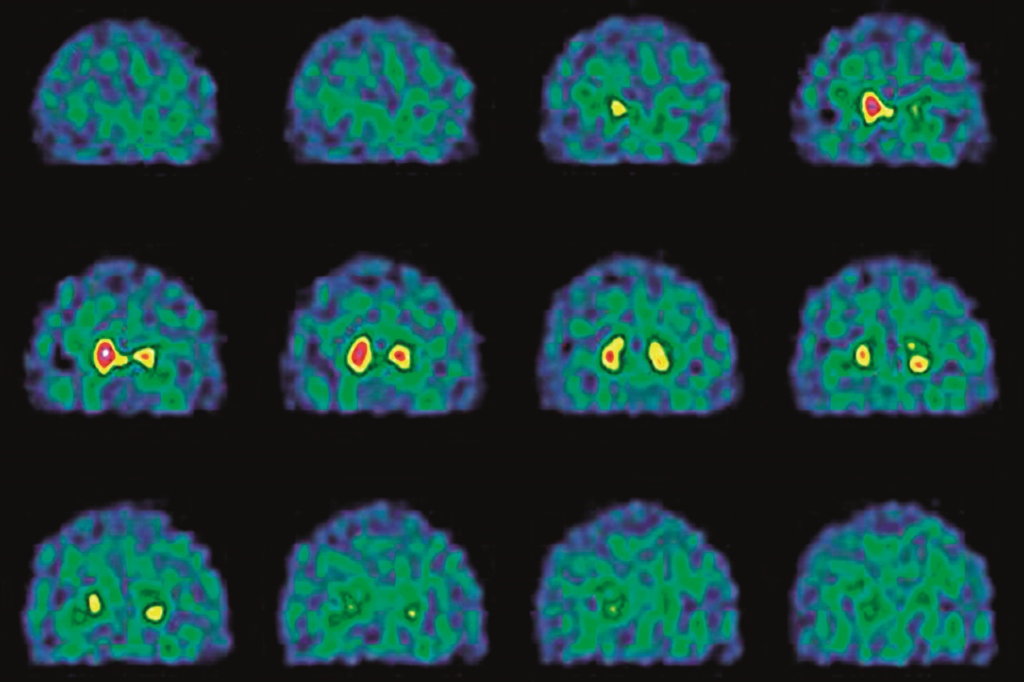

Furthermore, visual representations like the one above help us fully grasp the concept of Health Coaching With Ai For Parkinson'S Disease Management.